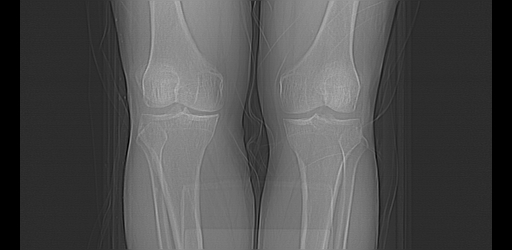

标题: CT13225:老年男性,左膝关节疼痛数月;请各位老师讨论。 [打印本页]

标题: CT13225:老年男性,左膝关节疼痛数月;请各位老师讨论。

骨质增生,骨性关节面硬化,关节积液,考虑退行性骨关节病

双膝退变

骨质增生,骨性关节面硬化,关节间隙失常,关节积液,考虑退行性骨关节病.

这个病例诊断:退行性骨关节炎